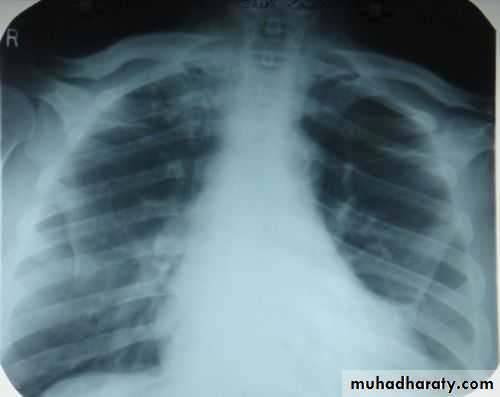

Techniques - Projection

P-A (relation of x-ray beam to patient)Supine view (AP)

P-A view , Other supplementary views are done according to the case. So all Patients admitted to hospital should have P-A X-ray In standing erect view in complete inspiration